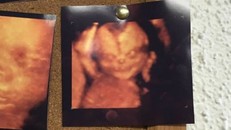

Lý giải những bức ảnh siêu âm thai nhi kì quái gây xôn xao

Những bức ảnh siêu âm thai nhi xuất hiện những khuôn mặt ghê rợn hay những hình thù kì quái được các nhà khoa học lý giải một cách rất đơn giản.